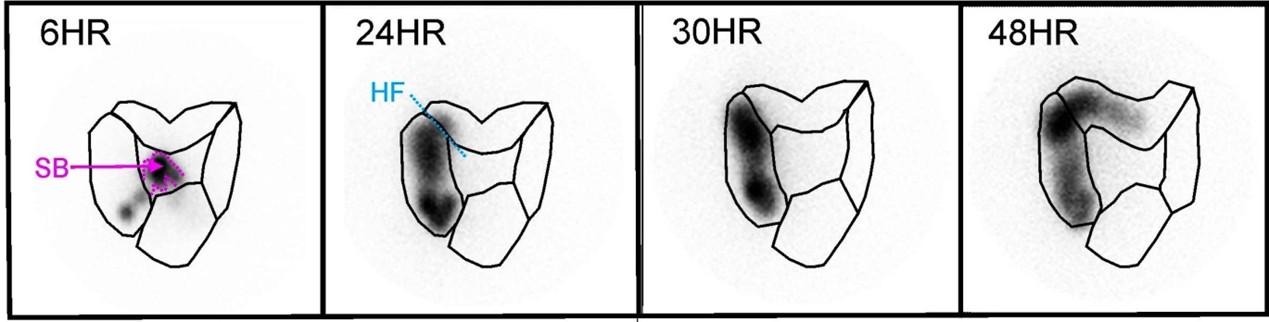

- Whole gastrointestinal transit scintigraphy (Figure 2): useful to determine gastric emptying, small bowel transit and colonic transit; 20% of children with chronic constipation will have dysfunctional gastrointestinal transit of the stomach, small bowel and colon; only available in hospital with Nuclear Medicine Department

Figure 2: Whole gastrointestinal tract transit study shows slow colonic transit

Figure 2: Whole gastrointestinal tract transit study shows slow colonic transit